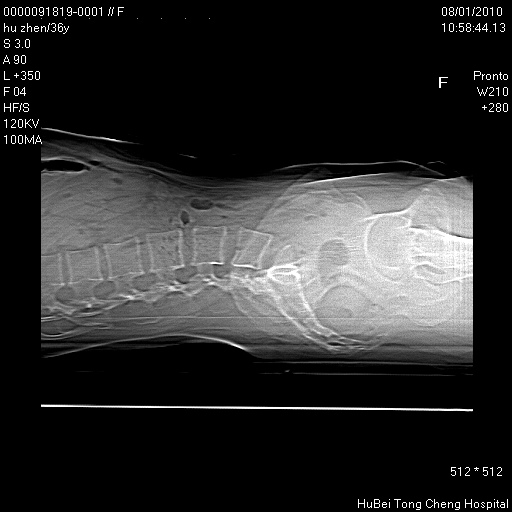

患者 女,36岁。右侧腰腿痛半月余。腰骶椎mr平扫偶然发现骶椎异常信号。

临床诊断:1)腰椎间盘突出症。2)骶椎肿瘤性病变?

骶椎ct平扫(层厚、层距均为5mm),图像如下: